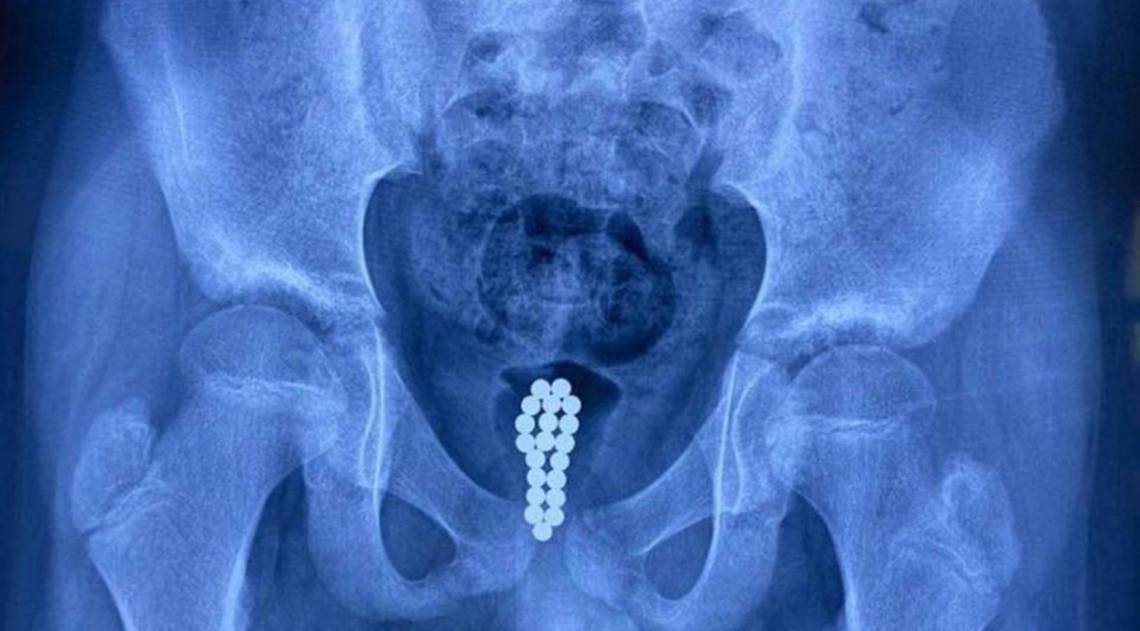

Honghui realizou uma cistoscopia - uma endoscopia da bexiga - durante a qual ele conseguiu contar os ímãs agora enferrujados no órgão da criança. "Mas como não conseguimos remover uma série de 20 esferas através de uma cistoscopia, optamos por uma cirurgia minimamente invasiva", disse em entrevista ao site.

O médico observou que a uretra era muito estreita para remover os objetos sem correr o risco de causar mais ferimentos. Mas a cirurgia foi considerada um sucesso.